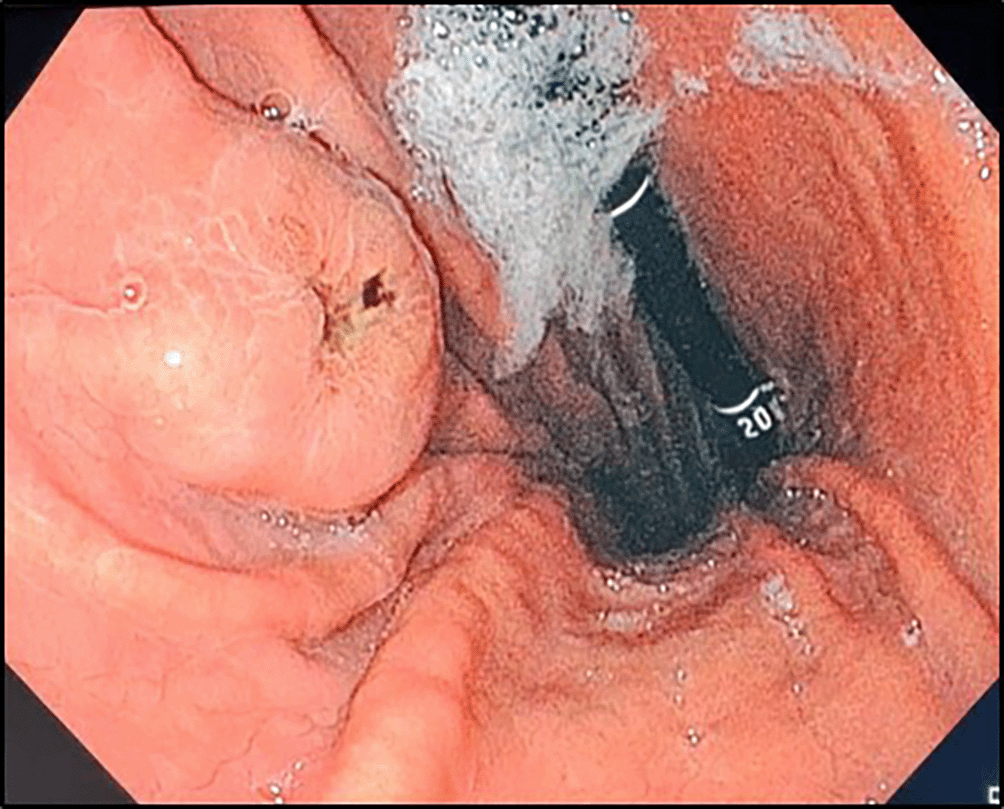

In the investigation for the primary cancer, and given the recent dyspepsia and epigastric pain, an upper gastrointestinal endoscopy was performed revealing a polypoid lesion at the antro-fundic junction measuring 20 mm in diameter, with a depressed and ulcerated centre, containing dark pigmentation ( Figure 2). The histological examination showed a tumour proliferation extensively invading the antro-fundic mucosa, composed of disintegrated cells, with deposits of brownish pigments. Immunohistochemistry analysis revealed positive staining for melanocytic markers Melan-A, S100 protein and HMB45 ( Figure 3). Other markers were negative, namely pancytokeratin, TTF 1, CD 45, chromogranin, and synaptophysin. These findings were consistent with a gastric localisation a melanoma.

Retroflexion shows an elevated lesion at the antrum-fundus junction with a depressed centre, resembling a volcano appearance, with brown pigments.

Nelson et al.10 proposed an endoscopic classification for GI melanoma metastases with three types: 1) melanotic nodules on normal folds with ulcerated tips; 2) elevated submucosal lesions with ulcerated centres, sometimes with visible melanin, often described as volcano-like or donut-shaped,9 as seen in our case; and 3) mass lesions with necrosis and melanosis. Such protruding lesions, especially with brown deposits, should raise suspicion for gastric melanoma. Other descriptions include polypoid masses, small nodules, and black spots.5,8,11